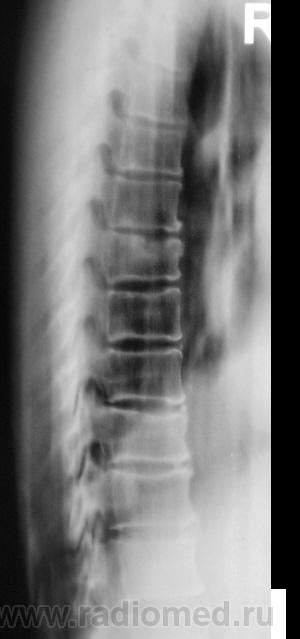

Если это женщина,старше 60 лет-обычная центральная грыжа Шморля при синильном остеопорозе.

Нет. Это мужчина. Возраст - 50 лет.

Тогда все равно грыжа Шморля :))))))))

Продольные полоски в телах позвонков тоже встречаю относительно часто. В книгах встречал 2 версии их происхождения: рудимент питающих артерий и форма перестроечной б-ни.

Похоже на большую грыжу, но мне кажется, что в ней что-то лежит, как сахарок тает? Не получится ли продолжения процесса?

Не в коем случае нельзя сбрасывать со счетов ТБС поражение позвонка. Создается впечатление о переходе процесса на вышележащий позвонок.

... тогда Фанарджяна (по костям) - в утиль! Какая перестроечная болезнь - во всех позвонках, строго по центру!?

Конечно же, рудимент. пит. артерии!